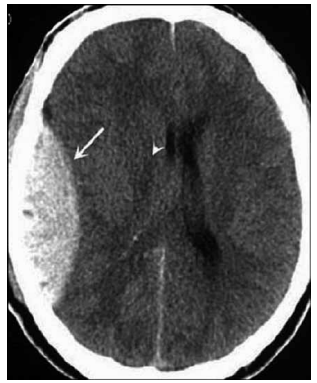

Homem de 68 anos apresenta lentificação progressiva

dos movimentos, rigidez muscular e instabilidade postural há três anos. Inicialmente, o quadro foi interpretado

como Parkinsonismo, mas a evolução clínica revelou

pobre resposta à levodopa, quedas frequentes, disautonomia e sinais cerebelares. A ressonância magnética do

encéfalo, a seguir, demonstrou atrofia do putâmen e do

cerebelo, com hipersinal na ponte (hot cross bun sign).

Diante desse quadro clínico, qual é o diagnóstico mais provável?